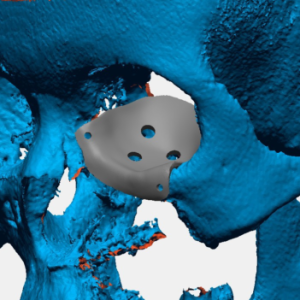

Mảnh ghép tạo hình hốc mắt

Mảnh ghép tạo hình hốc mắt

Vật liệu: vật liệu y sinh PEEK

Công nghệ: công nghệ in 3D

Thuộc đề tài/dự án nghiên cứu: Là sản phẩm của đề tài KHCN cấp TP. Hà Nội

Danh mục: Dạng chấn thương chỉnh hình

Mảnh ghép tạo hình hốc mắt

Vật liệu: vật liệu y sinh PEEK

Công nghệ: công nghệ in 3D

Thuộc đề tài/dự án nghiên cứu: Là sản phẩm của đề tài KHCN cấp TP. Hà Nội